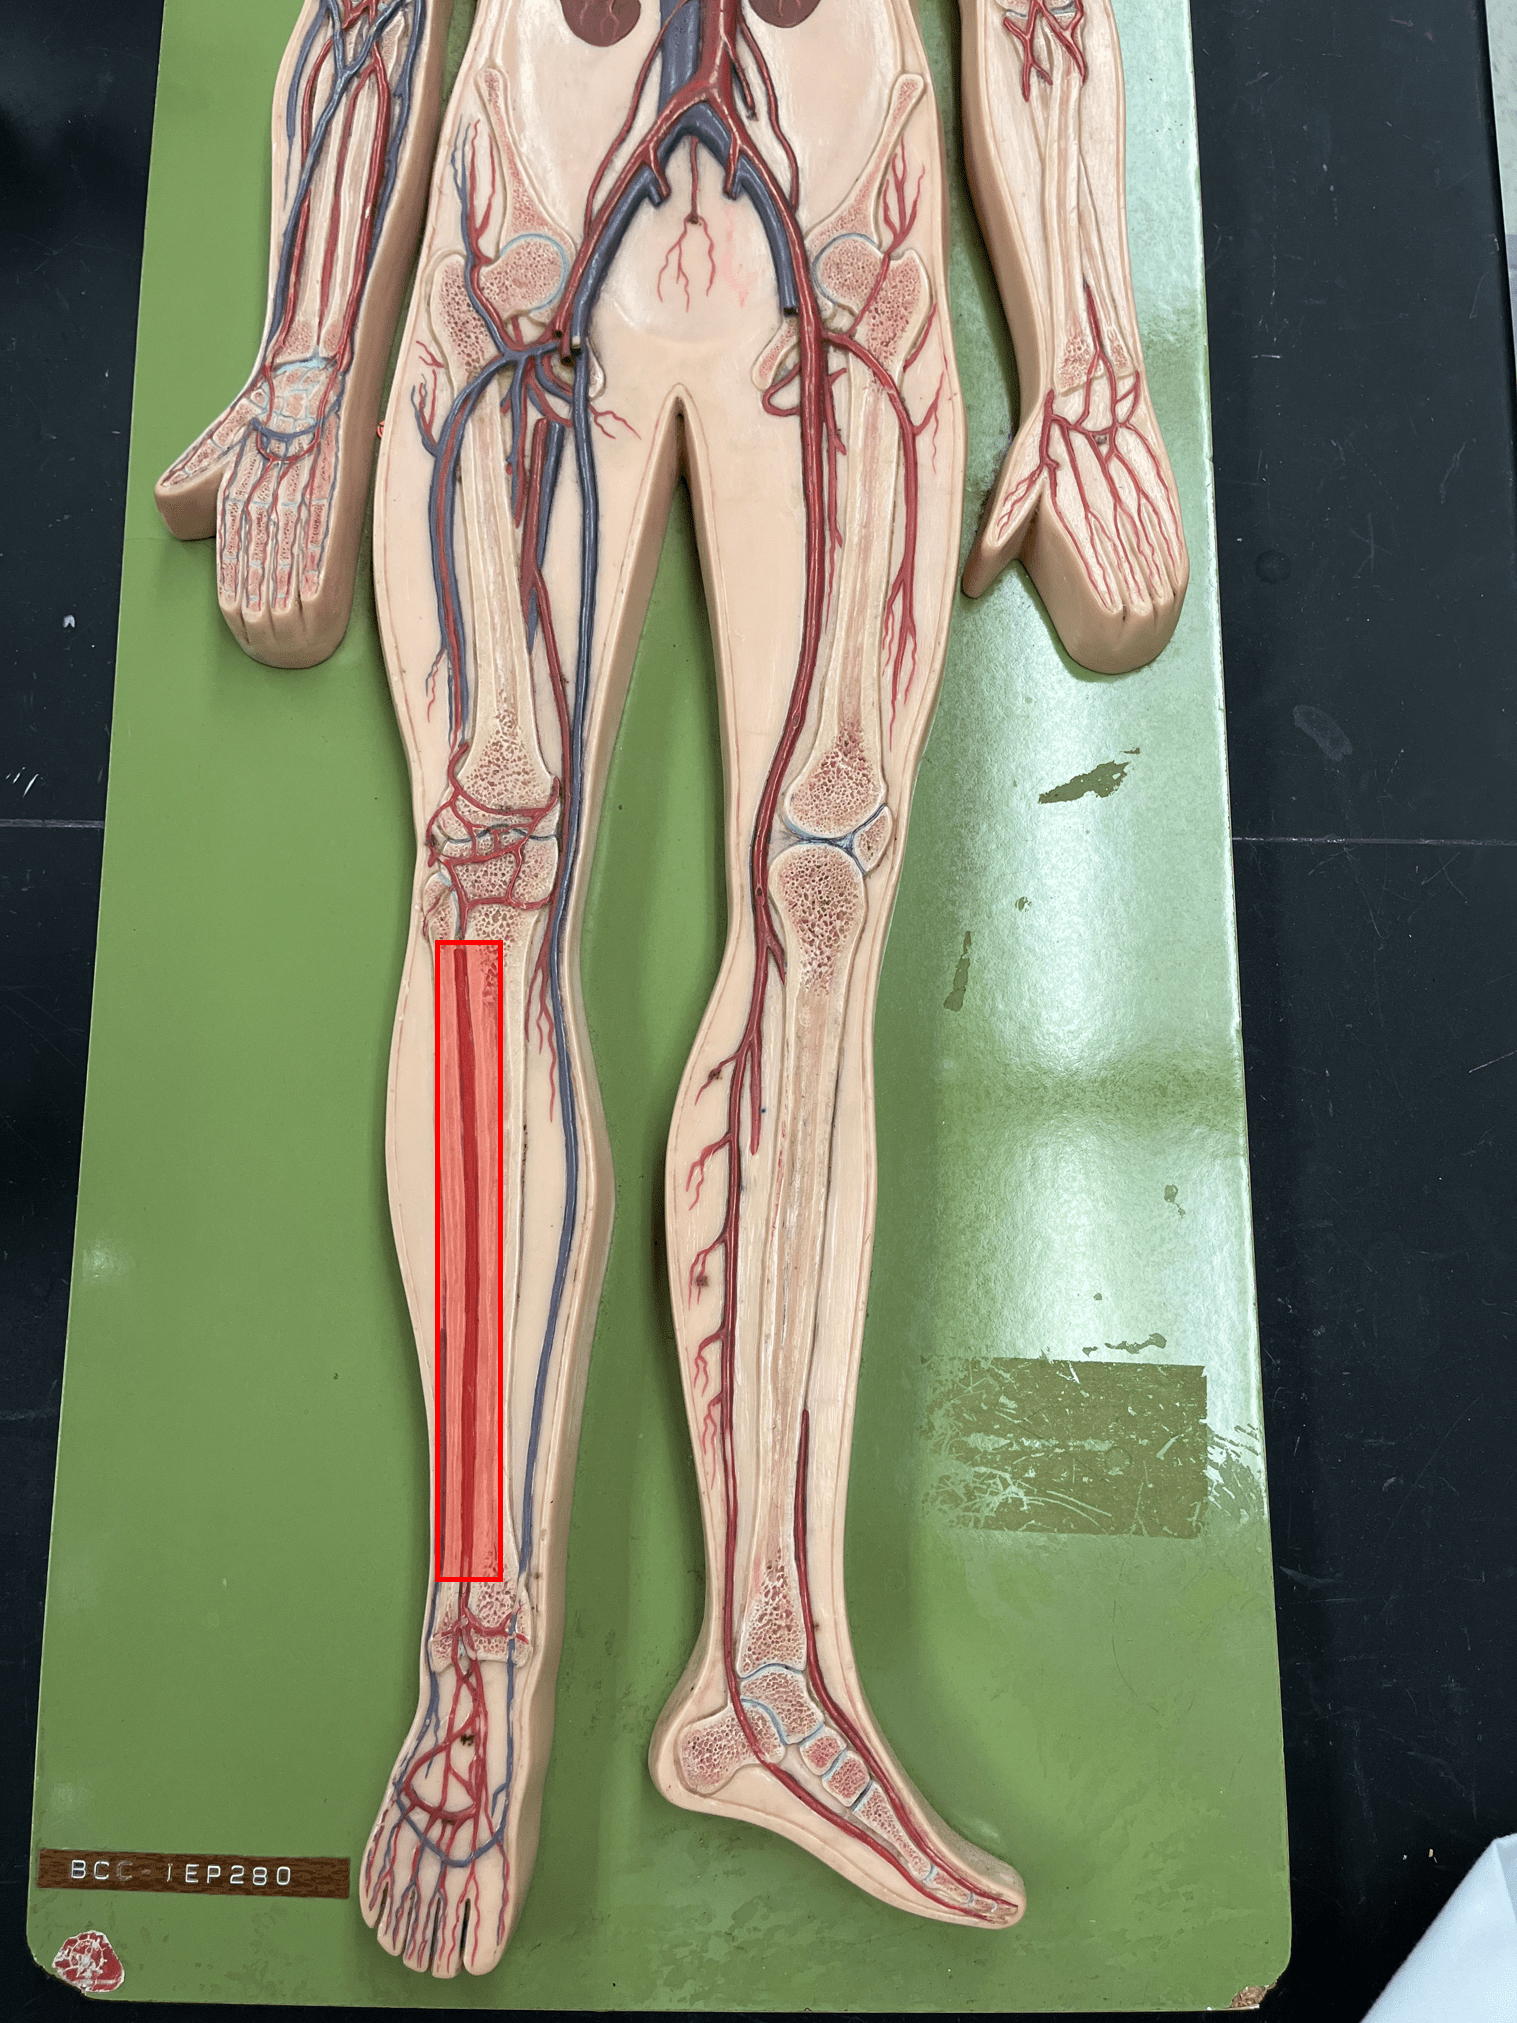

• An artery of the head and neck.

• Originates from the brachiocephalic trunk (R.) or the aortic arch (L.).